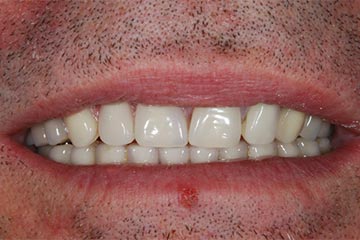

Con protesi fissa superiore e protesi fissa inferiore

I denti irrecuperabili dell'arcata superiore ed inferiore del paziente di anni 65

sono stati sostituiti da 10 impianti, cioè protesi radicolari endo-ossee che sostengono le protesi fisse superiore ed inferiore.